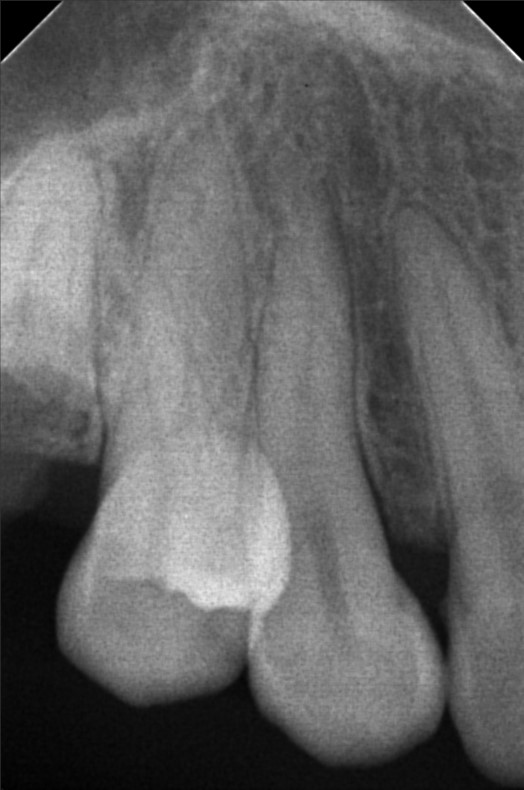

Edit Record Check our patient data records. Add patient information Patient Info Profile picture Last Name First Name Middle Name Birthdate Age Street Barangay City Country Zip Code Contact number Email Procedure 06/30/23- Informed Consent Ortho Check Up OP Impression Soft tissue analysis Intraoral photograph PA Radiograph For exo #15 Informed pt regarding class 5 cases Referred for cephalometric radiograph For resto class 5 #23, #24, #25, #35, #13, #14 10/24/25 oral prophylaxis xray tooth extraction #15 for restoration: abrasion: #23, 24, 25, 26, 14, 33, 35, 36, 44 recession: #13, 12, 11, 21, 22, 34, 32, 43 File atecotech2i712f_f.jpeg File 2 atecotech2i18f6_f.jpeg File 3 atecotech2i2a08_f.jpeg File 4 atecotech2i6330_f.jpeg File 5 atecotech2i278f_f.jpeg File 6 atecotech2i5dba_f.jpeg File 7 File 8 File 9 File 10 File 11 File 12 File 13 File 14 File 15 File 16 File 17 File 18 File 19 File 20 Retain Record Retain Record Yes No Save Your Changes